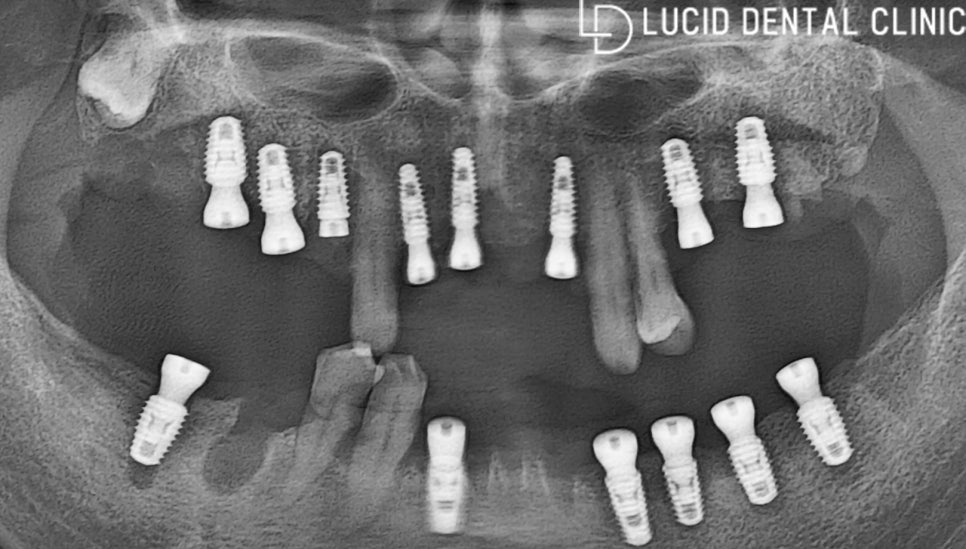

그 후, 신논현역 루시드 치과 에서 시행하는

디지털 컴퓨터 분석 프로그램 가이드로

계획된 위치에 맞춰 치조골에

픽스처를 즉시 식립하였는데요.

이대로 놔두면 제대로 식사하기 불편하겠죠?

조금 더 편안하게 식사하실 수 있도록

임시 보철을 제작하여 위에 씌워 드렸습니다 :)

이제 최종 보철을 제작한 뒤

위에 체결하기만 하면 되는데요.

그 전에 적지 않은 영향을 받았을 치은과

치조골이 온전히 회복될 수 있도록 기다려야 됩니다.